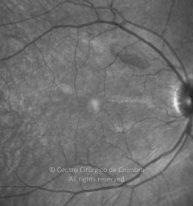

Paciente de 37 años con traumatismo contundente y ruptura del globo ocular. Presenta ruptura esclero-uveal, hifema, hemovítreo, desgarro periférico y temporal de la retina, hemorragias subretinianas y múltiples desprendimientos serosos.

MAVC: 20/25 OD, nueve años después de las cirugías (sutura escleral de la desinserción del músculo recto externo, vitrectomía posterior y fotocoagulación láser en el borde del desgarro retiniano, desprendimiento de retina inferior con proliferación vitreorretiniana y líquido subretiniano con algo de sangre; peeling de la membrana epirretiniana y maculorrexis de la MLI).